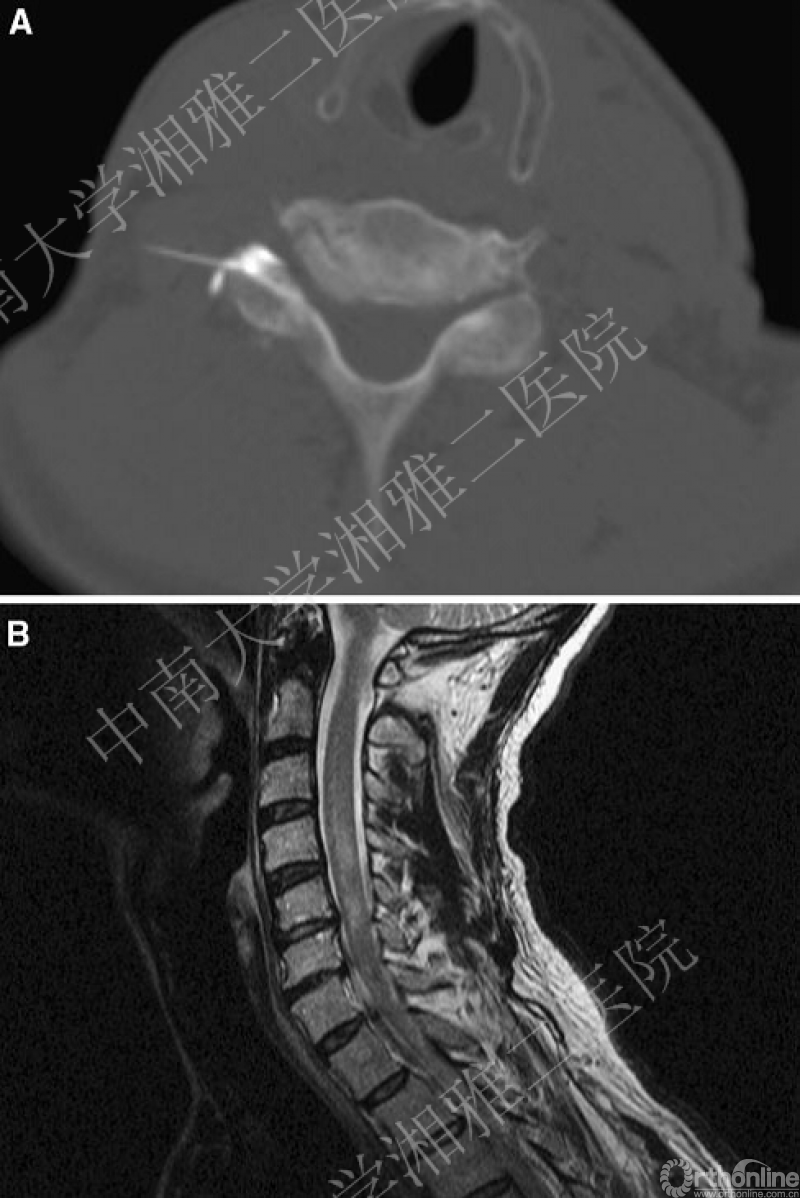

国内外临床应用文献报道很多,CTESI证据主要集中在有效性方面,而安全性证据极少。近年来零散的病例报道显示[3-8],CTESI具有灾难性中枢神经系统损害风险(图4)。CTESI相关严重不良事件的病例报道有9例,分别是X线引导经椎间孔CTESI导致小脑缺血和脑干嵌顿疝1例、X线引导C6神经根阻滞导致颈髓缺血性四肢瘫1例、X线引导经椎间孔ESI引起大面积小脑缺血梗死1例、X线引导C1~2小关节阻滞引起脊髓后动脉缺血梗死1例、C5~6左椎旁激素注射引起C2~3颈髓前部缺血并死亡1例、CT引导经椎间孔ESI引起小脑和脑干缺血梗死1例,X线引导经C7椎间孔ESI因为左侧椎动脉穿孔损伤导致死亡1例、CT引导经椎间孔ESI引起小脑和脑干缺血梗死2例。单纯注射局麻药也能出现问题[9,10]!

所有这些神经系统灾难性不良事件都与“颗粒型”激素有关,其可能的机制是“颗粒型”激素误入神经根伴行的根动脉,通过交通动脉进入并堵塞脊髓前动脉;另一个机制是颈段的颈升动脉(发自甲状腺下动脉)和颈胸交接处的颈深动脉(发自肋颈干动脉)参与和组成脊髓前动脉,穿过椎间孔时,通过穿刺针损伤此处的动脉血管,“颗粒型”激素直接进入了脊髓前动脉。当“颗粒型“激素进入堵塞细小的脊髓前动脉,由于缺少侧枝循环代偿,可以导致急性脊髓梗死[11,12]。“非颗粒型”激素,即地塞米松注射液,也曾引起短暂的失明和短暂的下肢瘫等不良事件报道,往往持续时间短暂且具有可逆性[13,14]。

图4:CT引导下经椎间孔造影并注射,术后发生高位颈段脊髓急性缺血改变